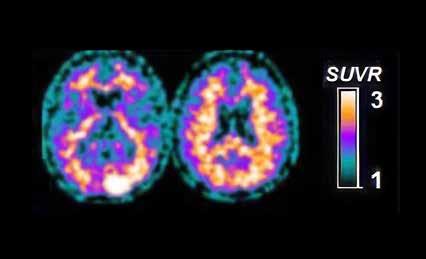

Sammenhængen mellem parodontitis og Alzheimers sygdom / 566

Vi ser på sammenhængen mellem parodontitis og Alzheimers sygdom, og om intensiv parodontologisk behandling kan medvirke til at forebygge og bremse demensudvikling.